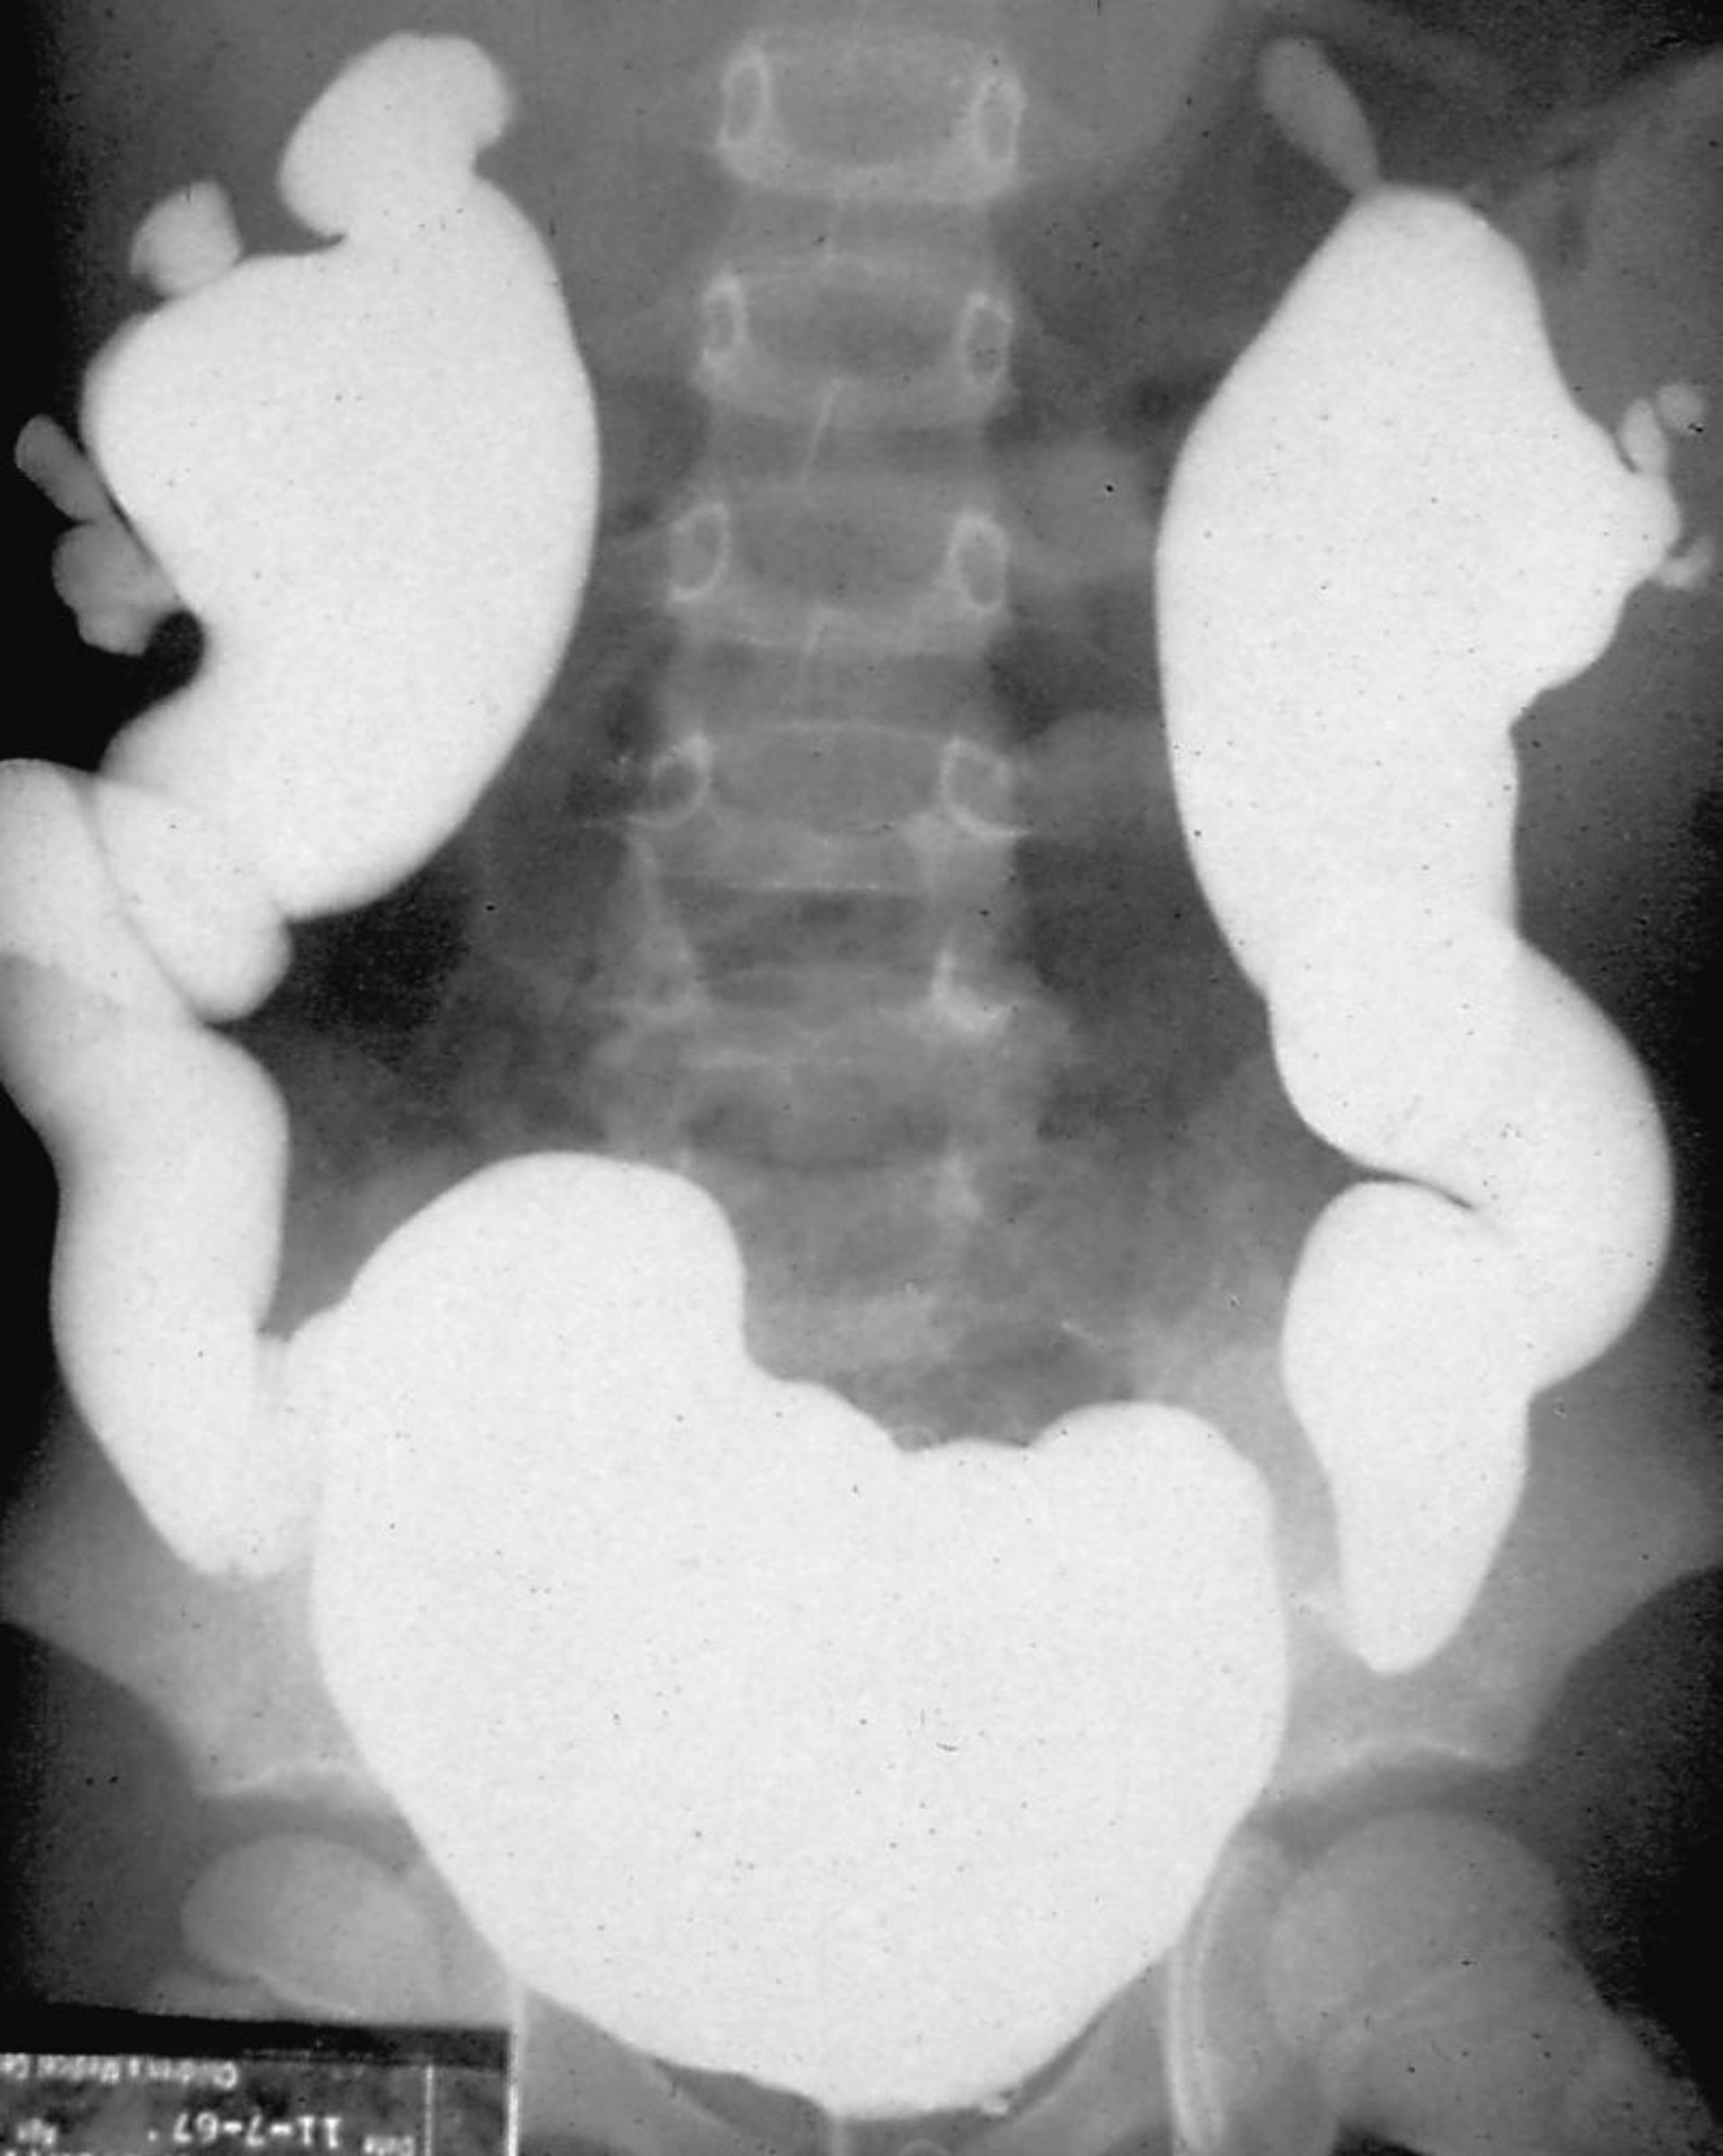

Bệnh thận do trào ngược (chụp bàng quang-niệu đạo khi đi tiểu)

Chụp cắt lớp vi tính bàng quang niệu quản được thực hiện bằng cách làm đầy bàng quang bằng chất cản quang và quan sát quá trình trào ngược dưới soi huỳnh quang, trong giai đoạn làm đầy bàng quang hoặc trong quá trình co bóp.